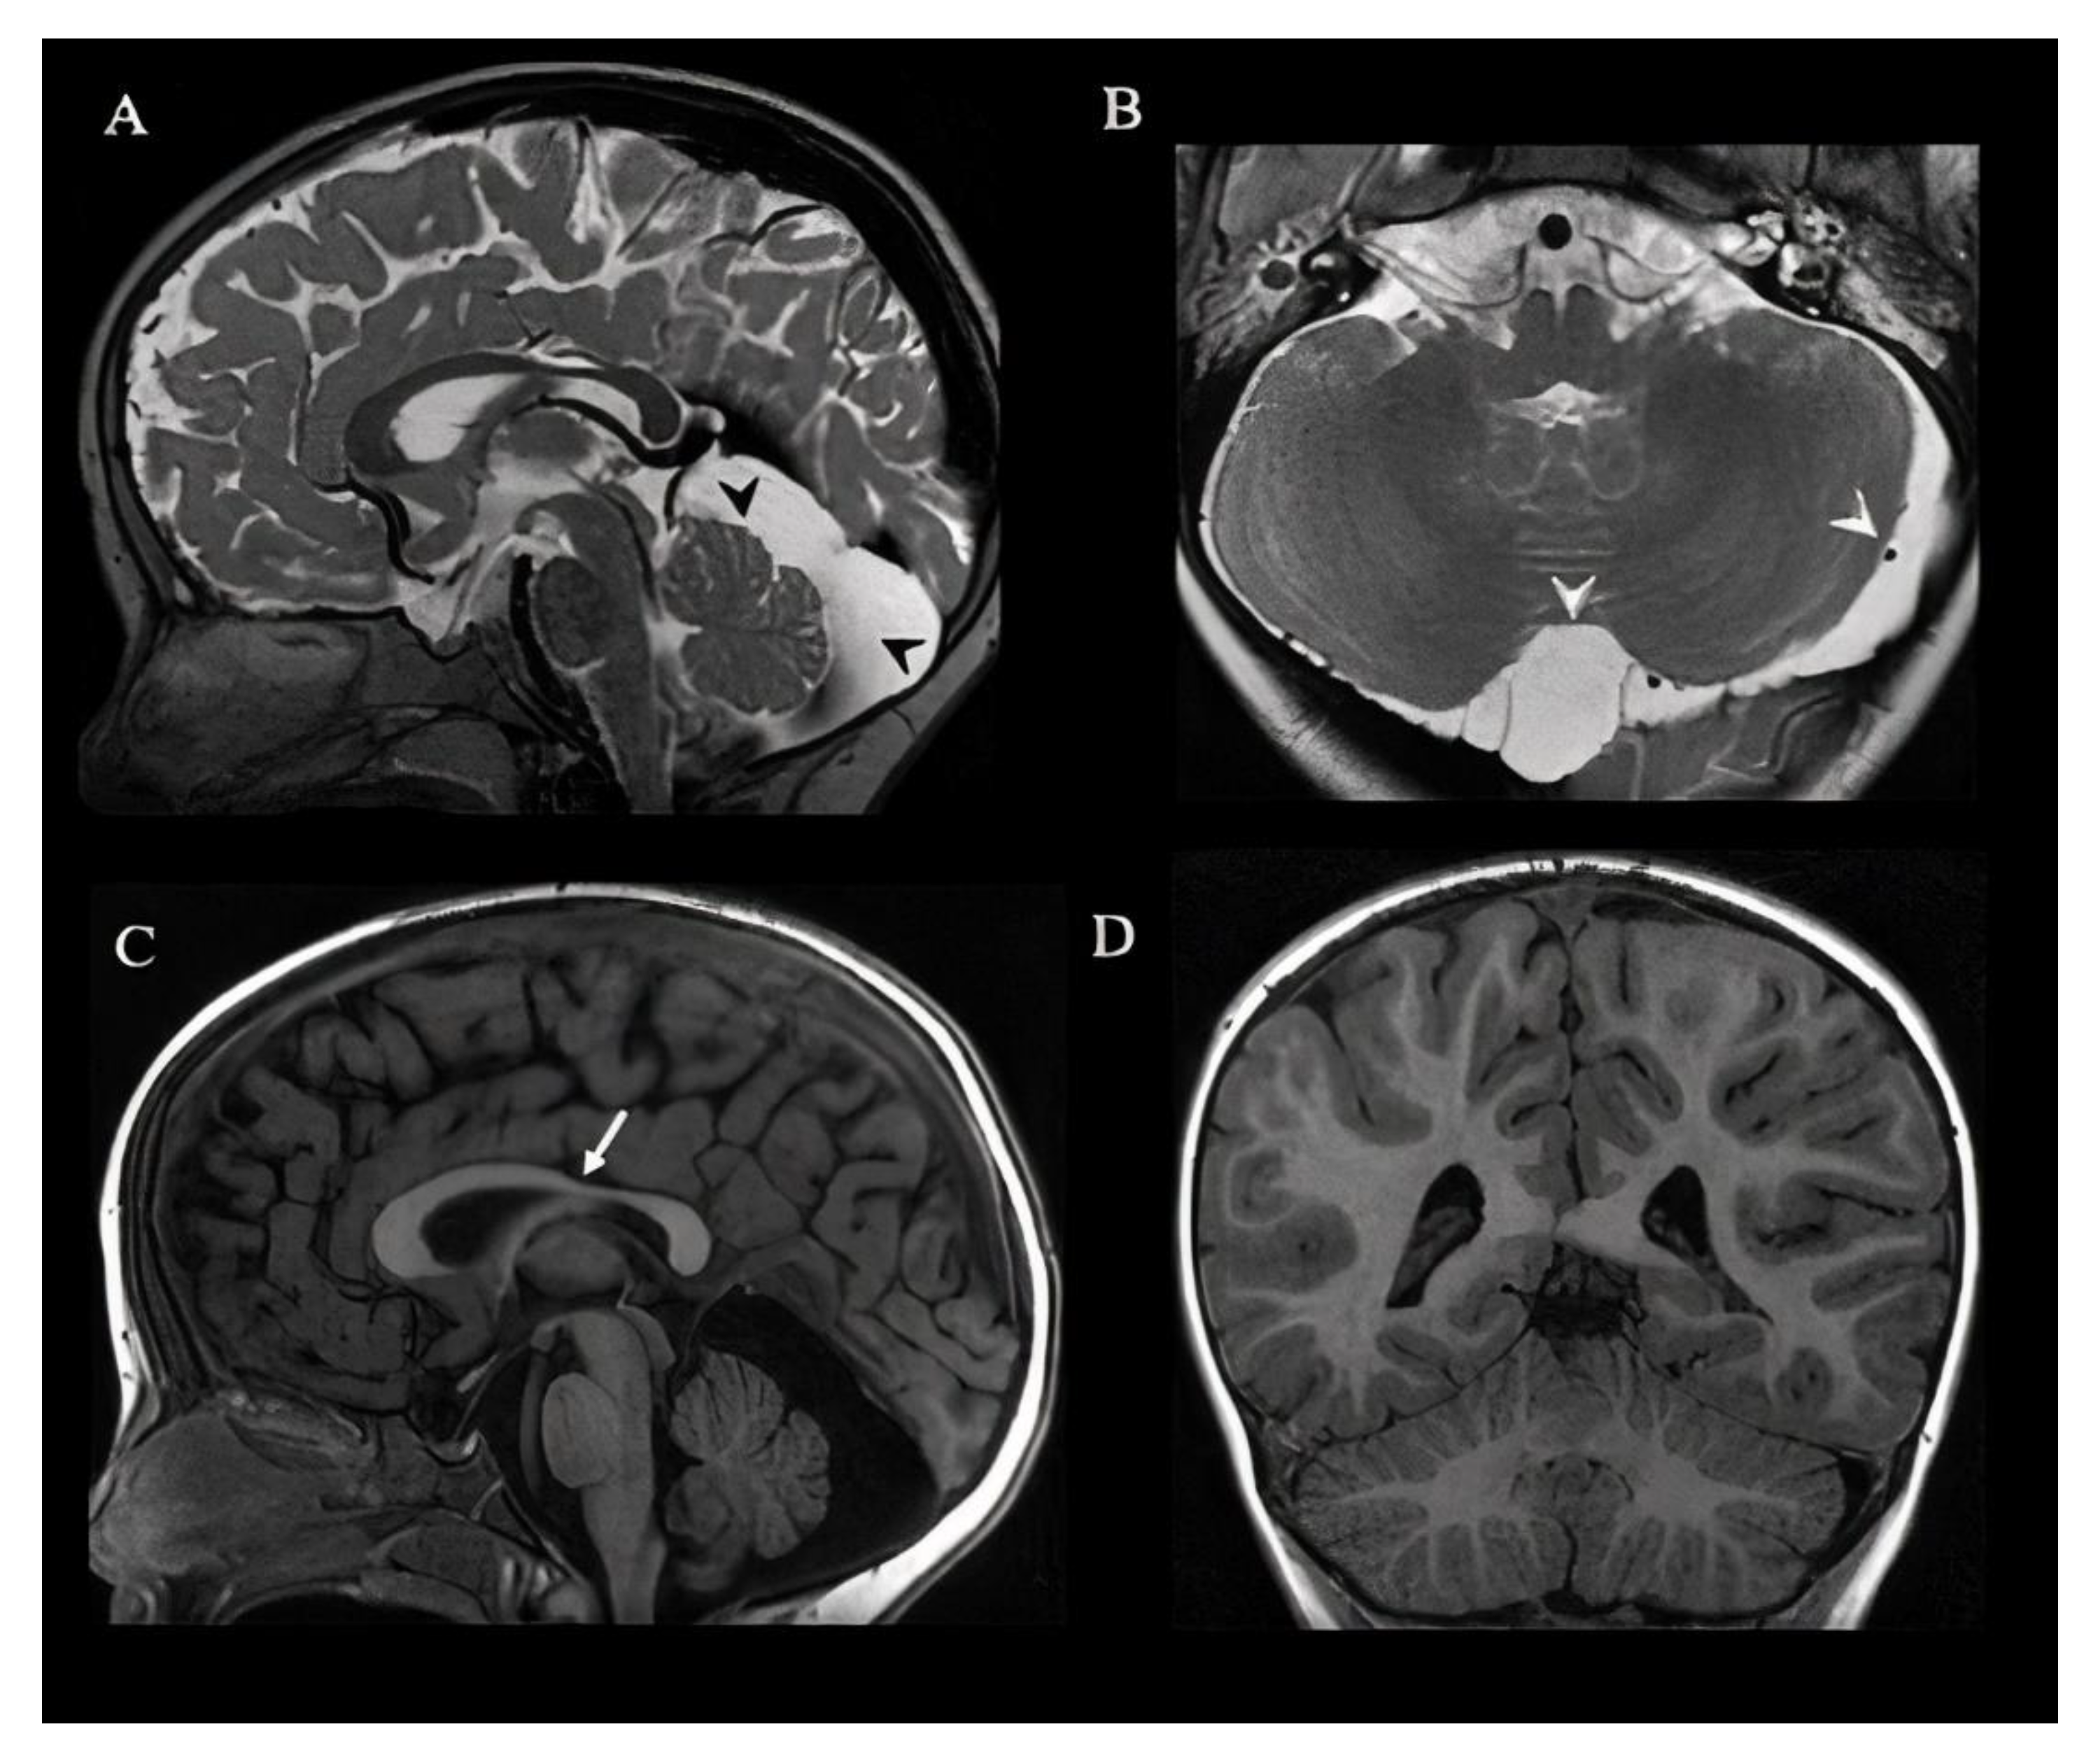

| Brain MRI | TCC, posterior fossa anomalies and asymmetric sulcation without cortical dysplasia | |